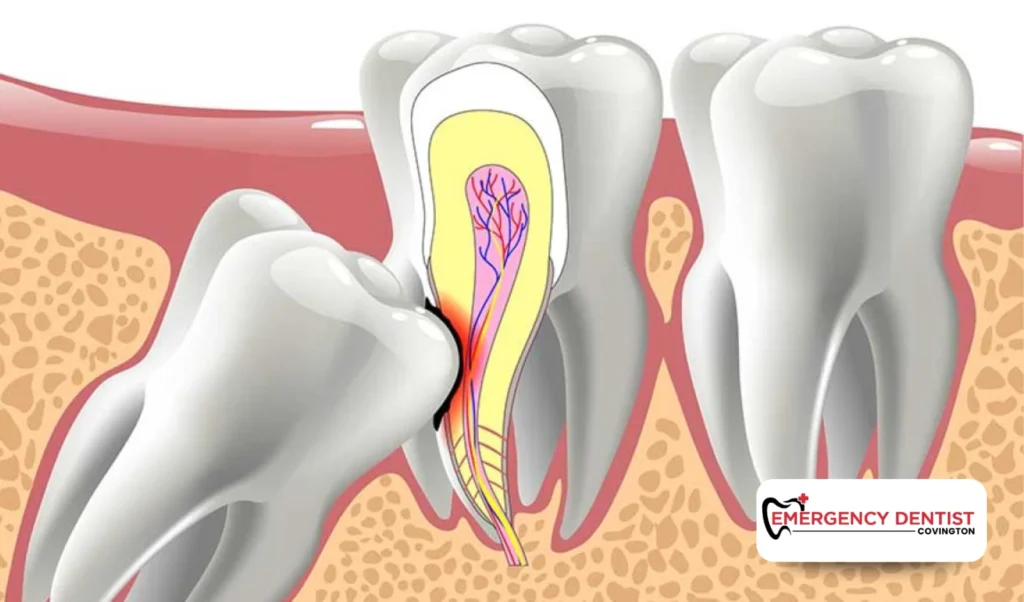

Why Wisdom Teeth Can Feel Uncomfortable

Modern mouths often do not have enough room for extra teeth. When wisdom teeth try to grow in crowded spaces, they may not come in smoothly.

Impacted Wisdom Teeth Explained

- Impacted wisdom teeth remain trapped under the gum or jawbone

- An impacted wisdom tooth may press against nearby teeth

- Partially emerged teeth can trap food and bacteria

Over time, impacted wisdom teeth can increase the risk of gum disease and tooth decay, which may affect overall oral health if left unmonitored.

When Wisdom Teeth Removal May Be Discussed

Not everyone needs wisdom teeth removal, but some situations require closer monitoring. A dentist may talk with you about wisdom tooth removal or removing wisdom teeth if:

- Wisdom teeth are impacted

- Teeth are partially emerged and hard to clean

- Gum disease or tooth decay is developing nearby

- Wisdom tooth pain continues or worsens

Wisdom teeth removal is often recommended to help protect nearby teeth and support long-term oral health.